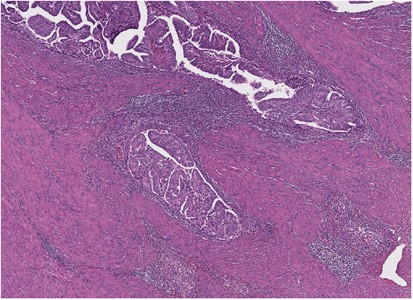

Fifteen of the 25 (60%) cases were of FIGO grade III/high grade. Intra-tumoral heterogeneity was noted in 13 of the 25 (52%) cases. Twenty-one of the 25 (84%) EC-POLEs showed increased tumor-infiltrating lymphocytes and/or peri-tumoral lymphocytes (Figures 1 and 2). There was one case (case 4) that showed lymphoepithelioma-like morphology (Figure 3).

The TCGA study and University of Calgary study demonstrated that patients with EC-POLE have a favorable outcome as compared with those with tumors of other genomic subtype.1, 8 None of the EC-POLE patients in these series developed disease progression, despite commonly being of high histological grade. As Meng et al8 and Heitzer et al21 had previously speculated, this may be a result of the general or specific mutation burden conferred by the ultramutated phenotype and the dramatic increase in base substitutions, which could be incompatible with tumor cell growth and survival. Furthermore, it has been shown that increased levels of tumor-infiltrating lymphocytes are associated with favorable outcome,25, 26 and the majority but not all (84%) EC-POLEs cancers analyzed here showed high levels of tumor-infiltrating lymphocytes and peri-tumoral lymphocytes.